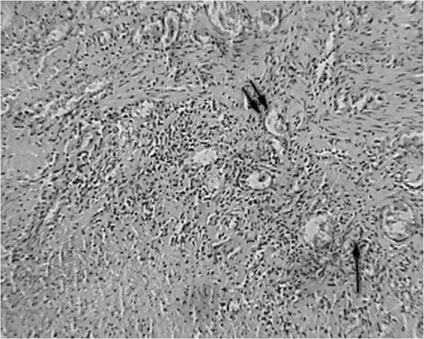

A szövettani vizsgálat a nyelőcső eltávolítása után végzett 3 esetben, a széleit a nyelőcső-mediasztinális sipoly után fibroezofagoskopii - 1 fő esetében. nyelőcső változások a stent minden esetben azonos, és képviseli a gyulladás különböző súlyosságú. A nyálkahártya talált szabálytalan hangsúlyos acanthosis, bazális réteg hiperaktivitás, dyskeratosis fejlesztésével a granulációs szövet a proximális és disztális végei a stent. A nyálkahártya alatti réteg feltárt infiltrációja limfociták, plazma sejtek és a makrofágok (ábra. 7).